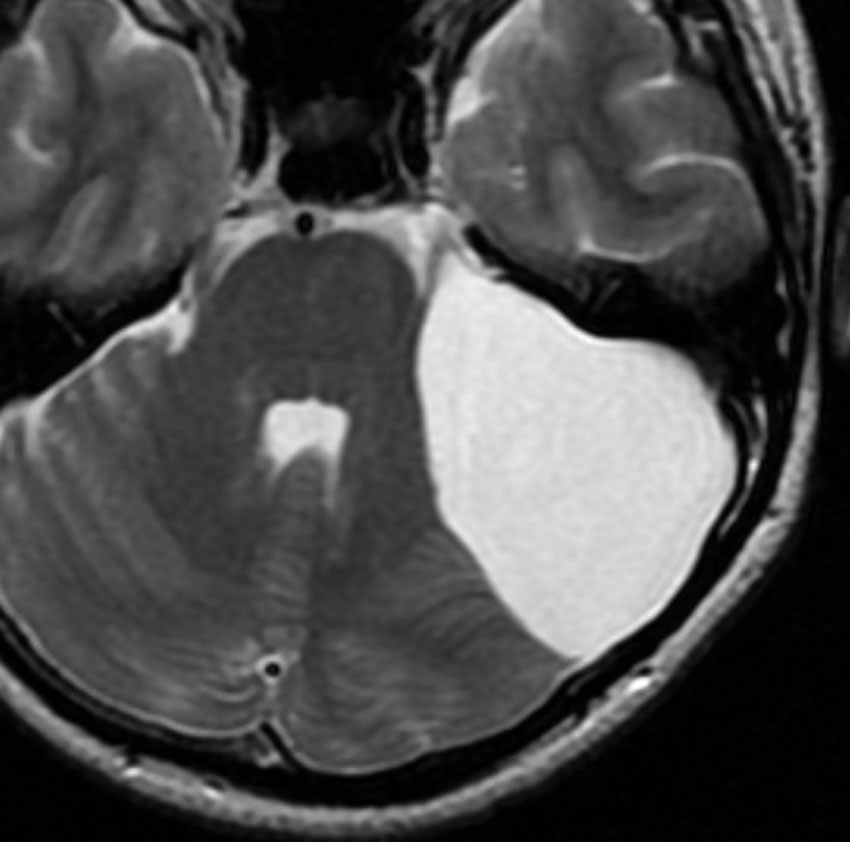

テント下くも膜のう胞

高齢の女性のくも膜のう胞です。テント下,上小脳槽にある大きなくも膜のう胞です。小脳扁桃ヘルニアになり,脊髄空洞症を併発しています。第4脳室出口の閉塞で水頭症となっていました。症状は数年かかって徐々に進行した歩行障害で,転倒しやすくなったとの主訴で受診しました。これは,のう胞壁を開頭手術で摘出する必要があるものです。数十年もある大きなのう胞ですから,意外に周囲の脳槽は狭いものです。実際に顕微鏡手術で,迂回槽と交通をつけるようにのう胞壁を除去したのですが,髄液交通を確保するのはとても難しいものでした。内視鏡ではリスクが高いかもしれません。